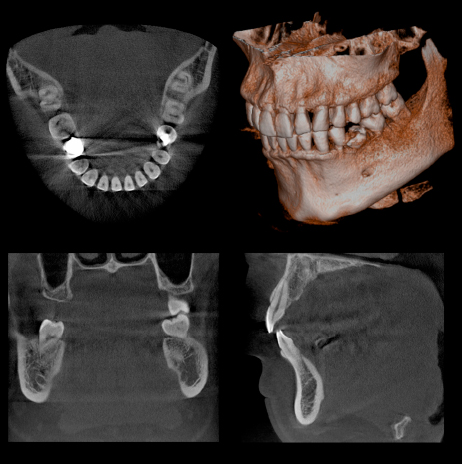

当院ではまだまだ個人の歯科医院での普及率が低い、CT(コンピュータ断層撮影機)を導入いたしました。

通常のX線撮影では、歯やアゴの骨の状態を二次元でしか確認できないため、色々な病状(歯の根の病気や歯周病の病状)を見落としてしまう可能性は否定でき ません。CTを撮影することによって、あらゆる方向から三次元で歯やアゴ骨の状態を確認可能なため、詳細な診断が可能になります。

撮影時間も9.4秒と極めて短く、放射線の被曝量は、医科用CT撮影(頭部)の1/77~1/23以下です。

限られた病変(歯の神経の治療、歯周病の治療、親知らずの抜歯など)においては保険適用での撮影が可能です。

また、インプラントの手術をする際には、アゴの骨の状態を診査するにはCT撮影が必要であり、その後の定期診査にも非常に有効です。

医科用CT撮影に比べると少ないながらも、被爆のデメリットもありますので、必要に応じて使用し、診査・診断に大いに役立てていきたいと思います。